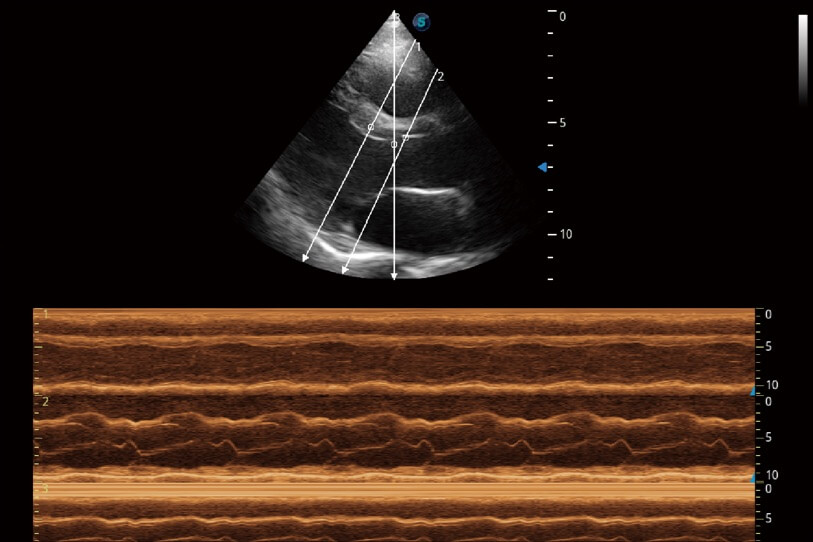

通過(guò)360度任意調(diào)節(jié)3條M型取樣線,在同一心動(dòng)周期上觀察心臟不同位置的運(yùn)動(dòng)曲線,得到準(zhǔn)確的心功能測(cè)量數(shù)據(jù),有效評(píng)估心肌運(yùn)動(dòng)及左心室功能。